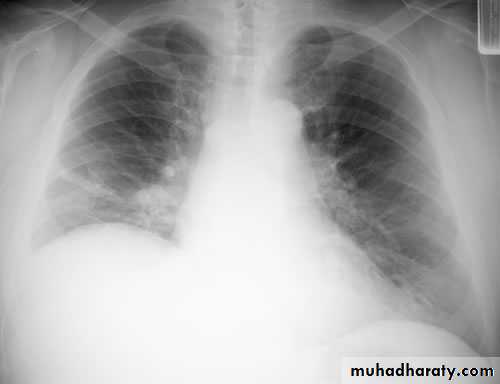

The main aims of investigations are to confirm the diagnosis, establish the histological cell type and define the extent of the disease.1- CXR: common radiological features of lung cancer:

Unilateral hilar enlargement.

Peripheral pulmonary opacity.

Lung, lobe or segmental collapse.

Pleural effusion.

Broadening of mediastinum, enlarged cardiac shadow, elevation of a hemidiaphragm.

Rib destruction.

Chest radiography shows multiple pulmonary nodules of varying sizes consistent with metastatic cancer.

Chest CT scan shows multiple round nodules and masses of varying sizes in both lungs, consistent with metastases. There are also small bilateral pleural effusions.

Multiple and bilateral secondaries